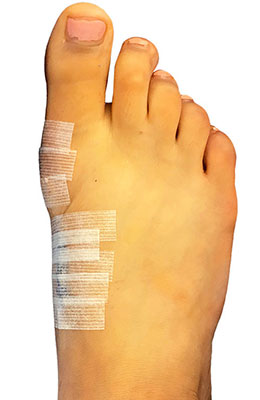

Before

Lapidus Forever Bunionectomy™ and Hamertoe Correction before

After

Lapidus Forever Bunionectomy™ and Hamertoe Correction after

Lapidus Forever Bunionectomy™ and Hamertoe Correction

Amanda is a 37-year-old mother who could not take much time off her foot and needed correction of a very large bunion (hallux valgus) that had also resulted in a hammertoe and partial discoloration of the 2nd toe joint. Amanda had a Lapidus Forever Bunionectomy™ and was back on her foot at 2 weeks after surgery and able to take care of her young children while she healed. Her bunion correction results are amazing, and her foot is fully back to normal.